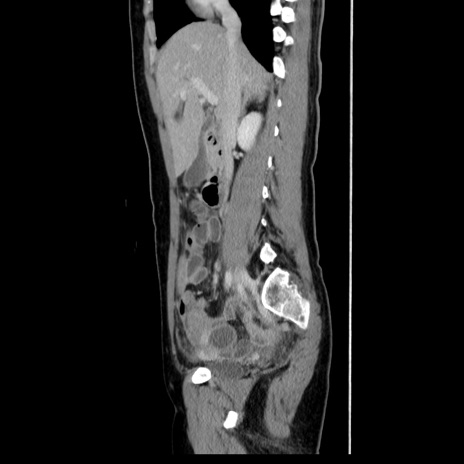

症例39(矢状断像)

【症例】40歳代女性

【主訴】上下腹部痛

【現病歴】2日目から下腹部痛あり。夜間は痛みで眠れなかった。昨日より上腹部痛と下痢が出現。臥位で痛みは軽快したため、休んでいた。本日になって臥位でも立位でも痛みが強くなってきたため救急要請。

【既往歴】子宮内膜症

【身体所見】部:平坦・軟、左上下腹部に圧痛あり、反跳痛あり。

【データ】WBC 21800、CRP 26.78

CT